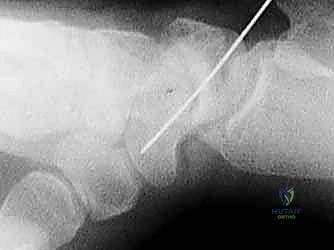

انزلاق رأس الفخذ الأعلى (SCFE): دليل شامل للعلاج والتعافي في صنعاء مع الأستاذ الدكتور محمد هطيف

تعرف على انزلاق رأس الفخذ الأعلى (SCFE)، أسبابه، أعراضه، وكيفية علاجه جراحيًا بدقة فائقة باستخدام المسامير المثقوبة. استشر الأستاذ الدكتور م…